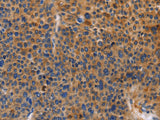

Applications IHC

IHC 1:50-1:200